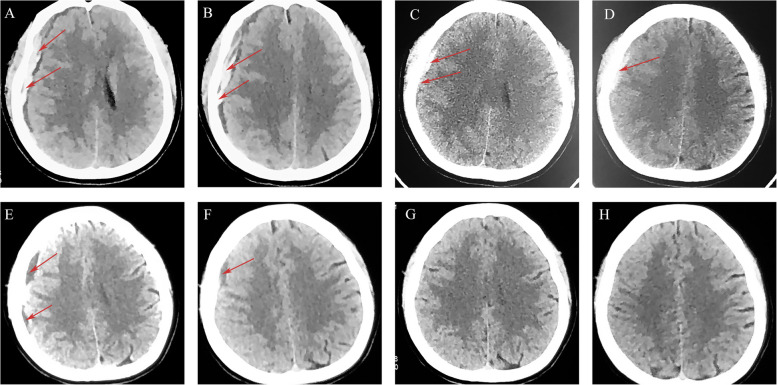

Case presentation: We selected five patients with sASDH who received a treatment regimen of atorvastatin plus low-dose dexamethasone without surgery. We then observed the clinical and radiological features during treatment and follow-up. The PubMed database and Google Scholar were retrieved for literature regarding the efficacy and safety of conservative treatment in patients with ASDH/sASDH. We extracted information including authors, sample size, gender, number of patients (death, poor prognosis, delayed surgery), and risk factors.

Results: Of the five patients, all patients who refused surgery for various reasons were resolved after treatment with atorvastatin plus low-dose dexamethasone for their conditions. No hematomas recurred or progressed during an at least 6-month follow-up. We identified 6 studies after searching the database; a total of 1374 patients (F:M = 3:7) with ASDH/sASDH received initial conservative treatment. The pooled results showed that 13.1% of patients who initially received conservative treatment deteriorated and required delayed surgical treatment. Of 1374, the overall incidence of poor prognosis was 19.2%, and 7% of patients eventually died.